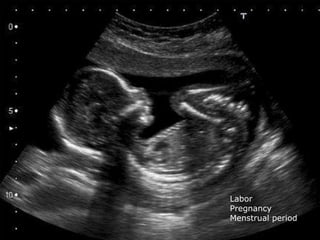

35 year old woman with 7 month history of LBP right

posterior thigh pain with new onset right vaginal numnbess

Cauda Equina Syndrome

Differential Diagnosis Back Pain

Not from the Spine

 Pregnancy

 Pregnancy with Labor

 Menstrual Period

Labor

Pregnancy

Menstrual period